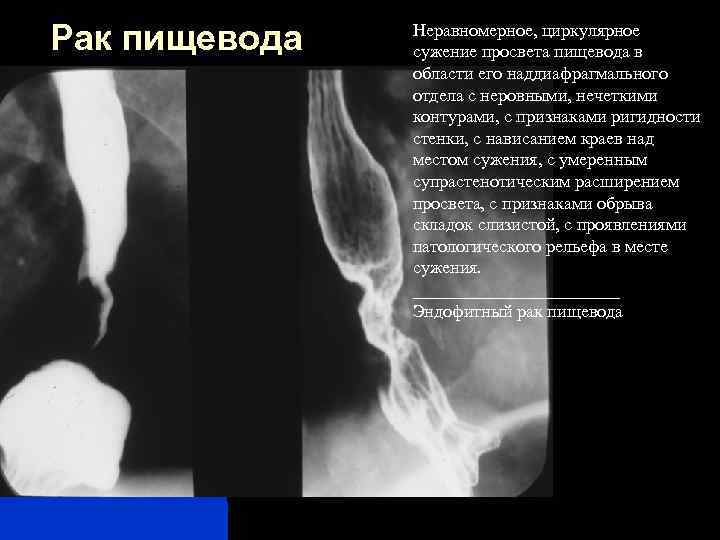

Злокачественные новообразования шейного отдела пищевода, выбор пластики